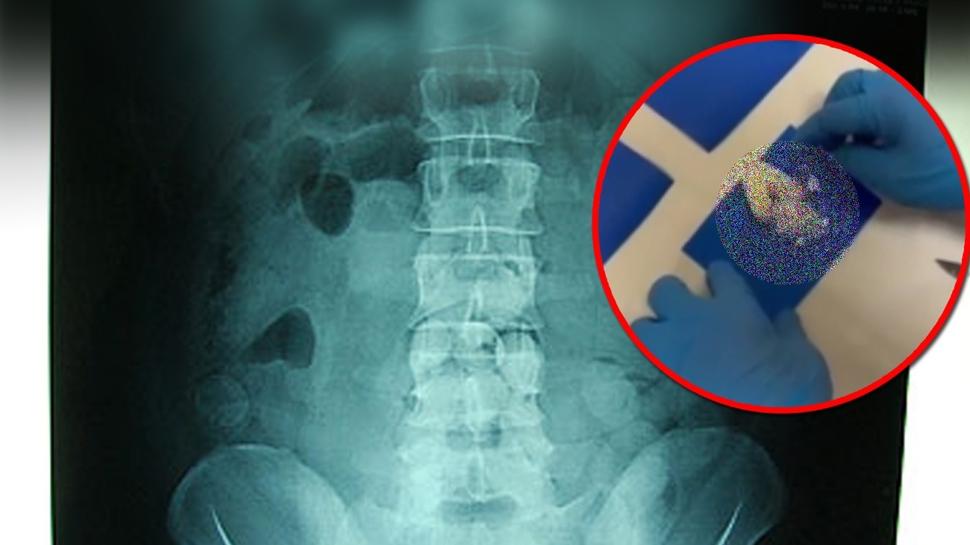

Türkiye'ye girerken tespit edildi! Midesinden bakın ne çıktı?

Midesine sakladığı uyuşturucuyu Türkiye'ye sokan şüpheli ile bu kişiye yardım eden 4 zanlı, Kastamonu'da gözaltına alındı.